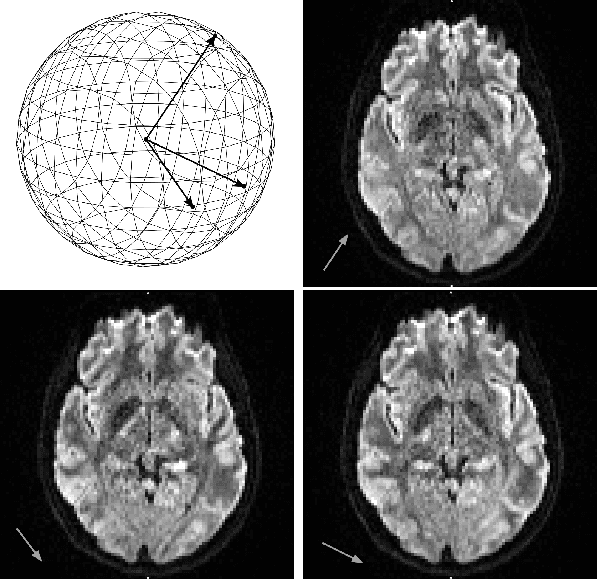

Diffusion MRI is a modern neuroimaging modality with a unique ability to acquire microstructural information by measuring water self-diffusion at the voxel level. However, it generates huge amounts of data, resulting from a large number of repeated 3D scans. Each volume samples a location in q-space, indicating the direction and strength of a diffusion sensitizing gradient during the measurement. This captures detailed information about the self-diffusion, and the tissue microstructure that restricts it. Lossless compression with GZIP is widely used to reduce the memory requirements. We introduce a novel lossless codec for diffusion MRI data. It reduces file sizes by more than 30% compared to GZIP, and also beats lossless codecs from the JPEG family. Our codec builds on recent work on lossless PDE-based compression of 3D medical images, but additionally exploits smoothness in q-space. We demonstrate that, compared to using only image space PDEs, q-space PDEs further improve compression rates. Moreover, implementing them with Finite Element Methods and a custom acceleration significantly reduces computational expense. Finally, we show that our codec clearly benefits from integrating subject motion correction, and slightly from optimizing the order in which the 3D volumes are coded.